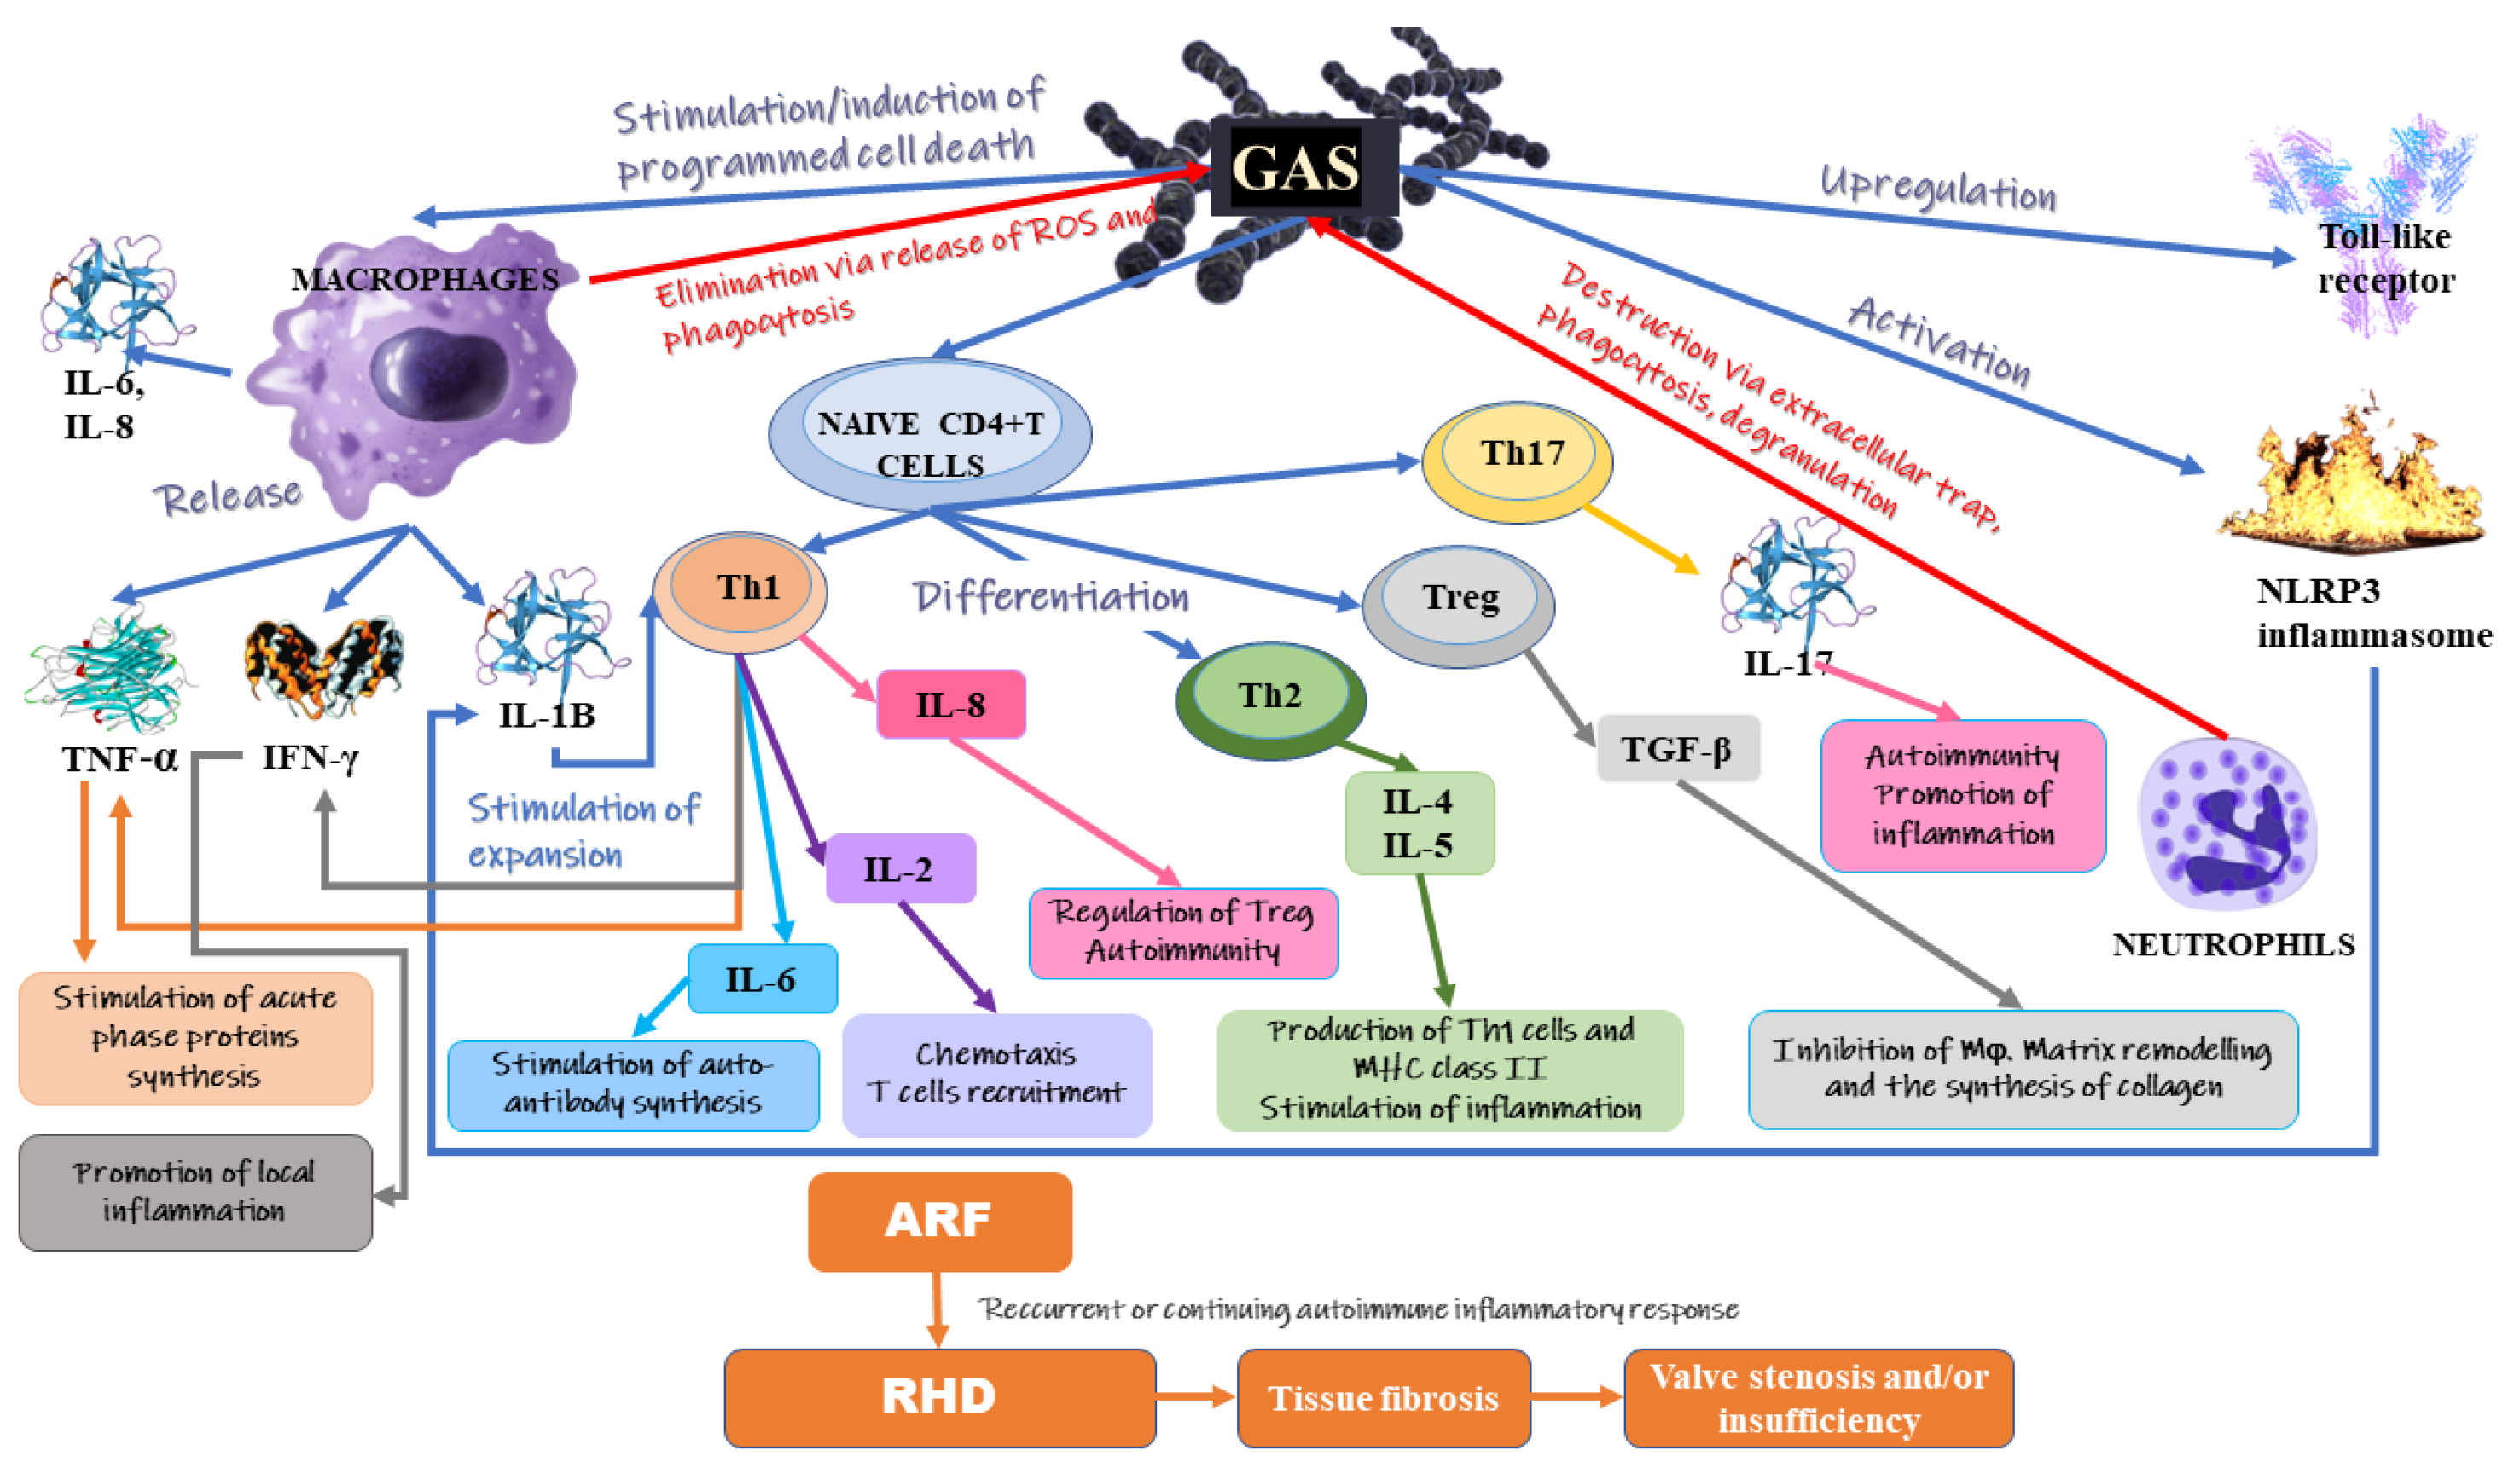

IJMS Free Full Text The Role Of Inflammation And Oxidative Stress

RHEUMATIC HEART DISEASE Define Etiology Risk Diagnostic

Rheumatic Fever And Rheumatic Heart Disease

Rheumatic Fever And Rheumatic Heart Disease